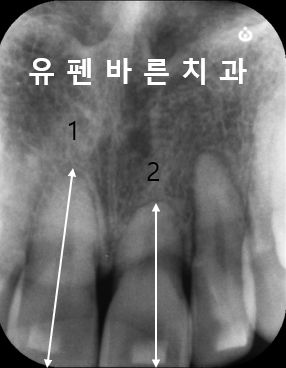

유독 뿌리가 짧았던

'2' 번 치아는

작은 엑스레이를 통해

주기적으로 체크를 함께 해주었어요^^